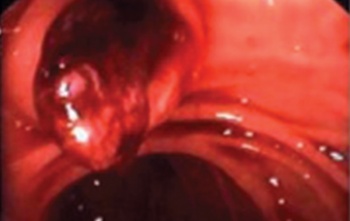

Upper GI endoscopy done during this admission showed blood within the distal stomach, and more fresh blood within D1 and D2 with blood coming from the ampulla of Vater. This confirmed the diagnosis of haemobilia. The liver biopsy was reported as mild inflammation and fibrosis without significant cirrhosis.

Figure 1. Blood coming from ampulla of Vater at upper GI endoscopy (click to enlarge)